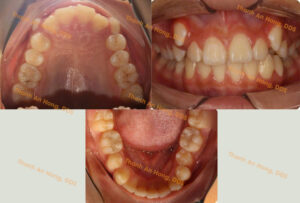

HÌNH ẢNH THỰC TẾ

Chỉnh mắc cài giảm hô

Sắp đều răng trong độ tuổi tăng trưởng với mắc cài